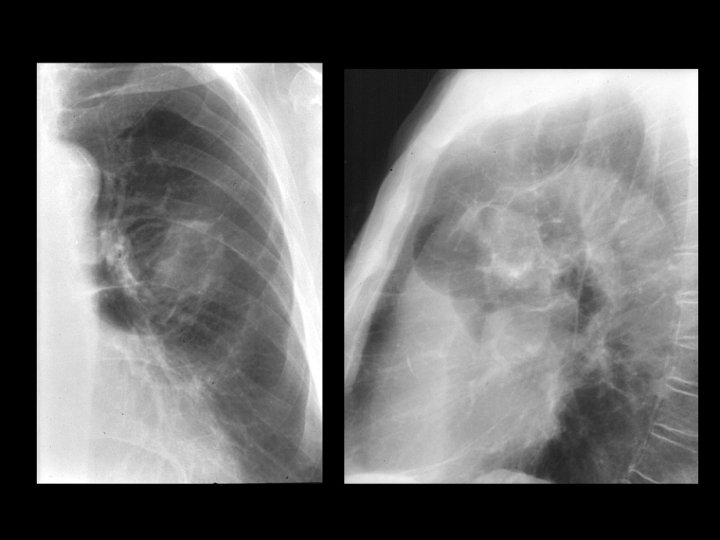

Findings and Differentials Findings: Frontal and lateral chest radiographs demonstrate a 3 -4 centimeter left upper lobe mass with surrounding areas of hyperlucency and arcuate parenchymal distortion. A healed left upper posterior rib fracture is noted. Four CT images show the irregular left upper lobe mass with peripheral attachment to thickened pleura. Note the parenchymal distortion in association with the inferomedial aspect of the lesion. Differentials: • Round atelectasis • Primary bronchogenic carcinoma

Discussion Round atelectasis (also known as rounded atelectasis) is a form of pseudotumor that often mimics a bronchogenic carcinoma. It is most often associated with prior asbestos exposure but can be caused by other insults including trauma. In theory, any process that results in development of a pleural effusion with associated atelectasis can result in round atelectasis. Specifically, if an effusion results in fibrinous adhesions to the atelectatic lung, subsequent lung trapping results in a “rolling up” of this portion of lung. As the effusion clears, the remaining lung in the region re-expands, leaving only the “rolled up”, trapped lung as evidence of prior effusion. Thus, round atelectasis is a peripheral process requiring adhesions with the pleura. As noted in the initial chest radiograph and associated CT images in this case, The arcuate parenchymal distortion in association with the mass represents bronchovascular structures trapped in the “rolled up” atelectatic lung. The inferomedial location of this parenchymal distortion with respect to the hilus of the mass has been termed the comet tail sign. Of the four choices given in the initial diagnosis section, the most likely options are round atelectasis and bronchogenic carcinoma. Round pneumonia is not common in adults, and the mass appearance is overall less typical for metastasis.